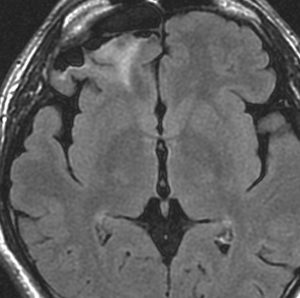

手術できない大きなグレード3でも治る期待がある

覚醒下手術などの積極的な手術をしてはいけない

若い女性の左前頭葉から島回,側頭葉を侵す腫瘍で,てんかん発作で発症し,開頭生検 biopsy しました。

一部で,細胞密度が高く,核の腫大とクロマチンの増量,核間距離の短縮があり,核分裂像が認められ,MIB-1染色率が10%です。組織学的には退形成性乏突起膠腫グレード3とされました。

IDH変異あり,1P/19q欠失あり,ATRX変異なしです。

乏突起膠細胞系グリオーマなので,放射線治療の高線量領域はあまり広くとりません。

IMRT Simultaneous Integrated Boost (SIB)で,FLAIR高信号の領域に54グレイ27分割,周囲仮定浸潤領域 generous local areaに46グレイを照射しました。

テモゾロマイド75mg/m2を併用しています。

左の画像は放射線治療直後のMRIですが,すでに腫瘍の縮小がみられます。

テモゾロマイドの維持療法は,24コース 2年間行い,それ以降は無治療としました。

照射後7年の画像です。腫瘍は縮小したまま,患者さんは無症状で経過しています。